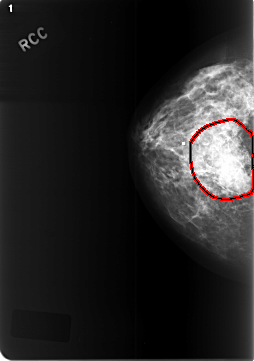

C_0471_1.RIGHT_CC

RIGHT_CC LINES 5768 PIXELS_PER_LINE 4056 BITS_PER_PIXEL 12 RESOLUTION 50 OVERLAY

FILE: C_0471_1.RIGHT_CC.OVERLAY

TOTAL_ABNORMALITIES 1

ABNORMALITY 1

LESION_TYPE MASS SHAPE ASYMMETRIC_BREAST_TISSUE MARGINS ILL_DEFINED

ASSESSMENT 5

SUBTLETY 5

PATHOLOGY MALIGNANT

TOTAL_OUTLINES 1

BOUNDARY